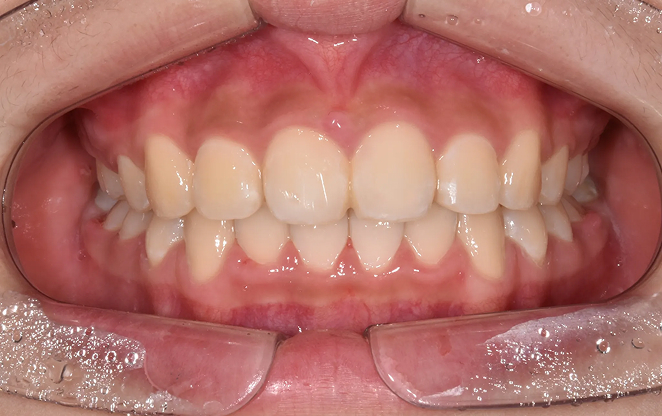

Before

After